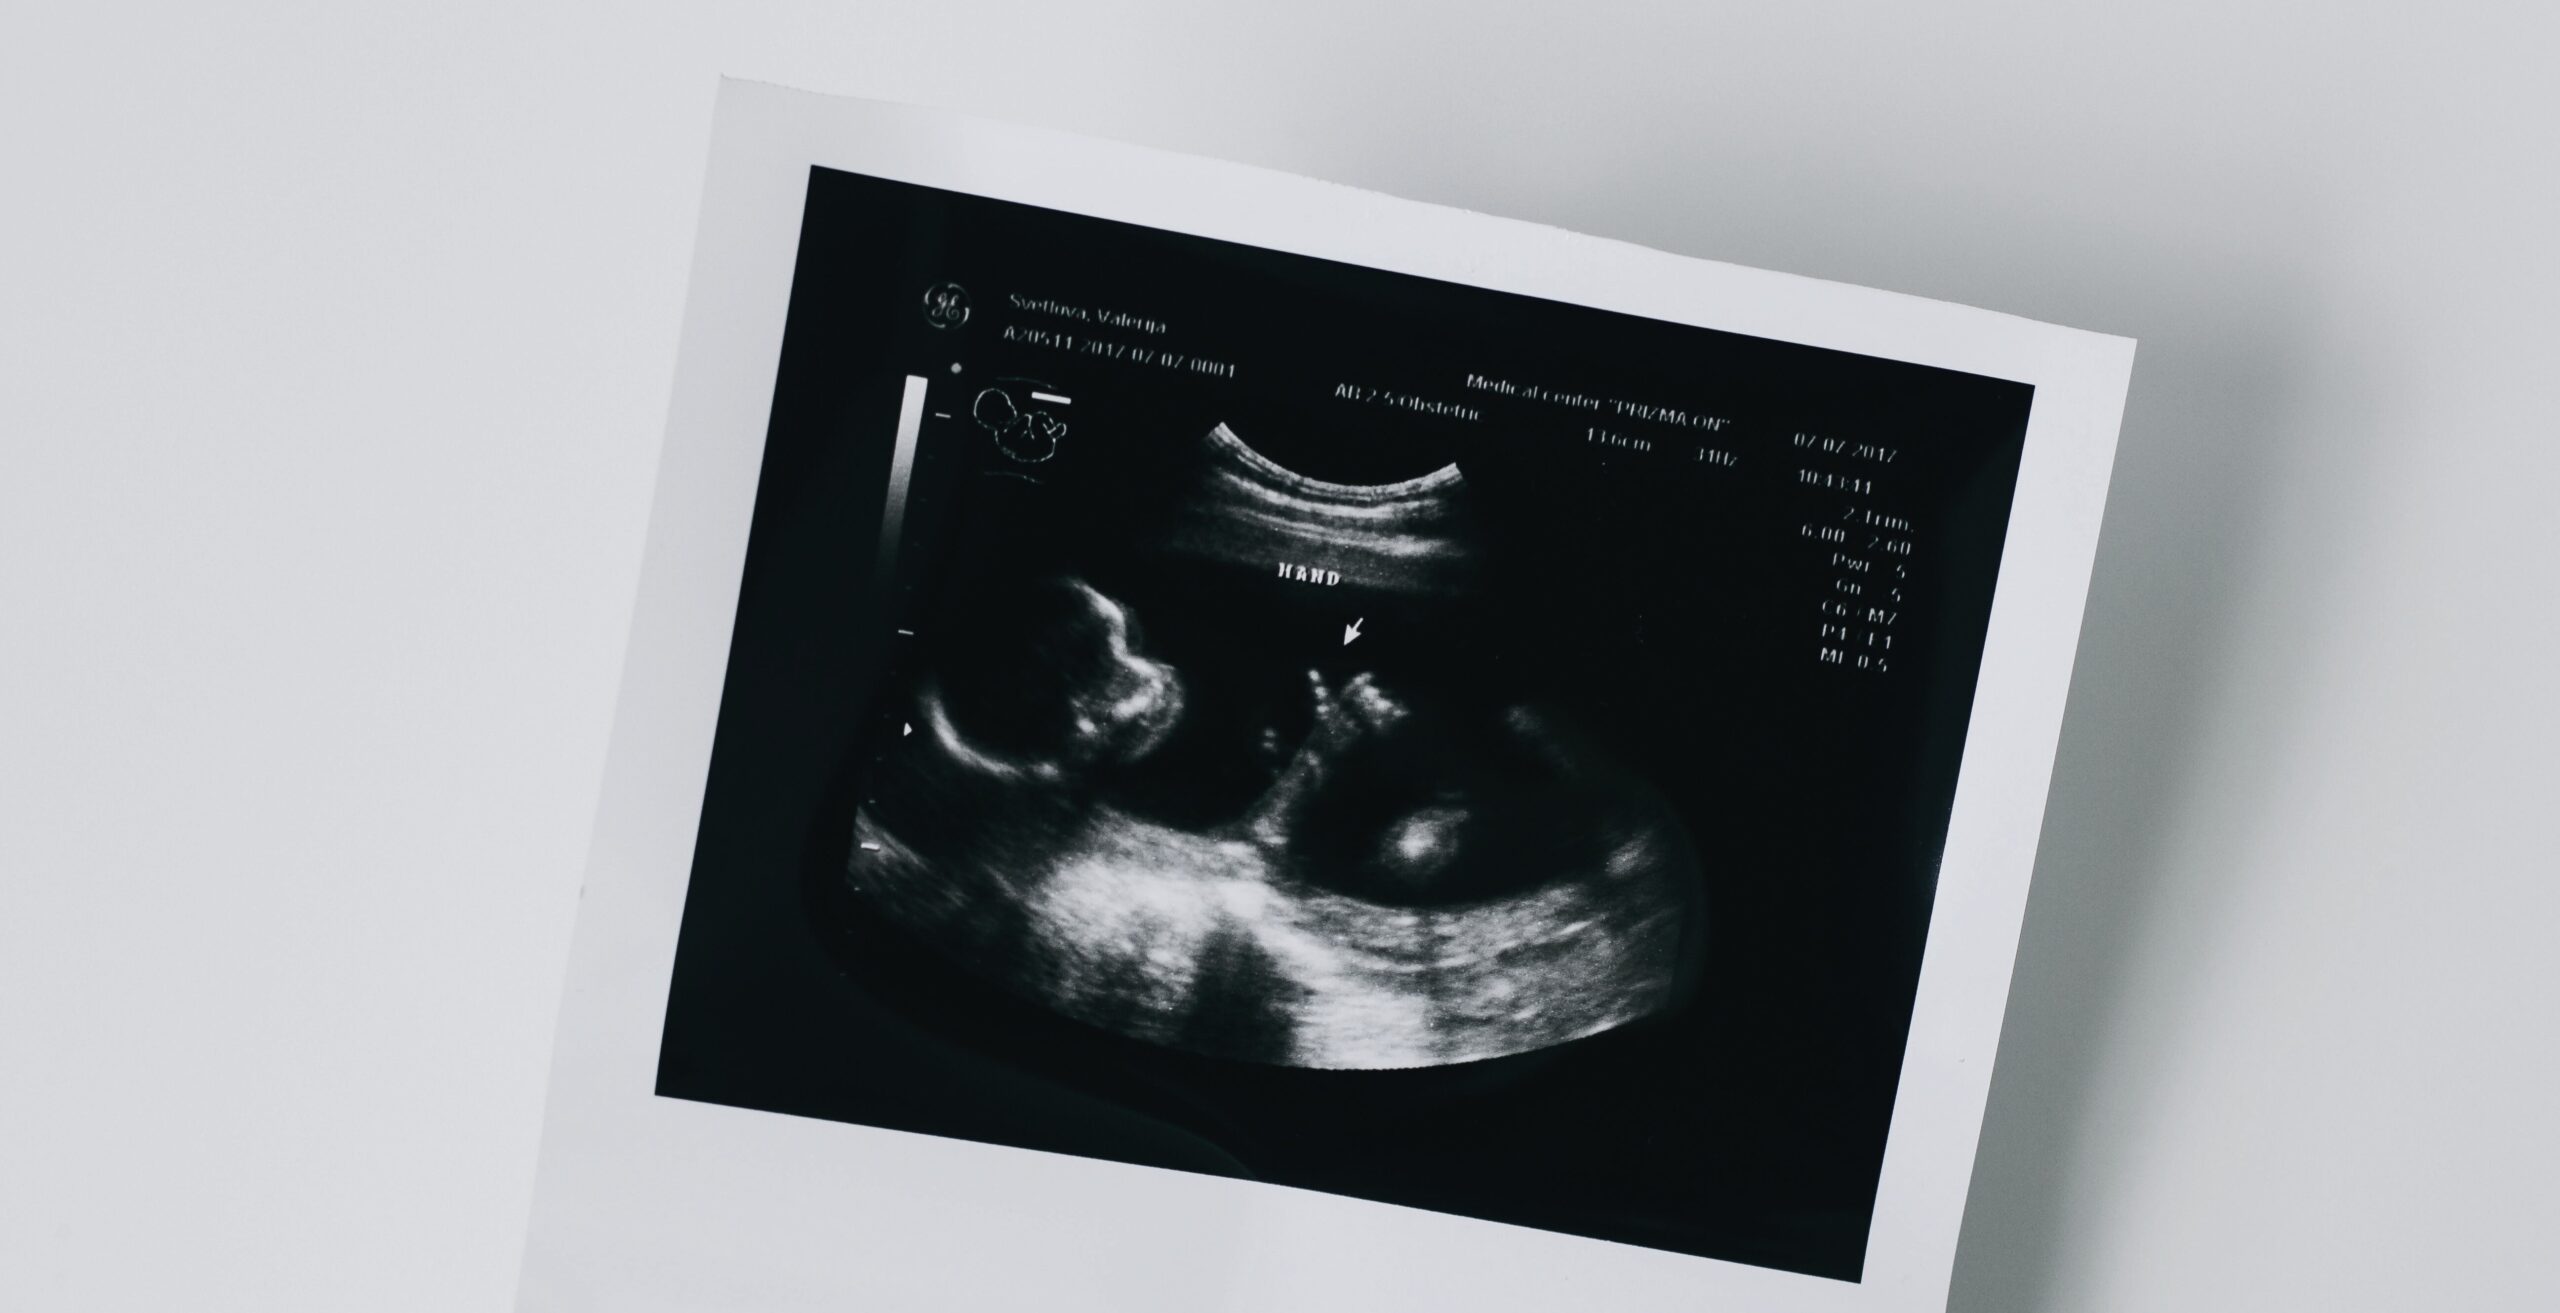

Képzeljünk el egy gyermeket, aki családfát készít az iskolában. A többiek mesélnek nagyszülőkről, régi történetekről – ő pedig nem érti, miért szorul össze a torka. Nem tudja, kinek az arcvonásait, mozdulatait, tulajdonságait örökölte. És nem is tudhatja, mert eleve úgy tervezték, hogy ezt soha ne tudja meg. Az anonim donoros lombikeljárás ezt a hiányt már a fogantatás pillanatában belekódolja a gyermek életébe: a származás titokká válik, a gyökerek rejtve maradnak.